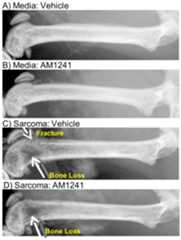

Radiographic images were taken following behavioral testing to determine the effect of AM1241 treatment on sarcoma-induced bone loss. Bones were rated with the following scale: 0 = normal, 1 = bone loss observed with no fracture, 2 = unicortical bone loss indicating unicortical bone fracture, 3 = bicortical bone loss indicating bicortical bone fracture (Luger et al., 2001). Radiographs were taken prior to surgery eliminating the possibility of baseline group differences. Throughout the time course of the experiment, bone loss was not observed in animals injected with media and treated with vehicle or AM1241. Sarcoma-induced bone loss increased in tumor bearing mice as compared to sham mice. Sarcoma treated animals with vehicle from day 7 to day 14 resulted in a significant amount of bone loss (Figure 3C). Sustained AM1241 from days 7 until day 14 significantly reduced the amount of sarcoma-induced bone loss when compared to the vehicle treated animals (P<0.001) (Figure 3D). Bones were scored by a blind observe with expertise in bone radiology. Animals with sarcoma and vehicle had severe bone loss with all animals having unicortical fracture (Figure 3E). Sustained AM1241 from day 7 until day 14 significantly reduced bone loss by blind scoring with only 2 out of 10 animals demonstrating unicortical bone loss (Figure 3E).

Fig 3.

AM1241 reduces sarcoma-induced bone loss. Representative radiographic images of femur injected with medium of sarcoma cells. The femurs were treated with vehicle or AM1241 Bone is reduced in tumor bearing animals treated with vehicle as compared to animals treated with AM1241. A) Bone injected with media and treated with vehicle. B) Bone injected with media and treated with AM1241. C) Bone injected with sarcoma cells and treated with vehicle. D) Bone injected with sarcoma cells and treated with AM1241. E) Bone rating scores demonstrating AM1241 treatment reduced the occurrence of unicortical bone fractures in sarcoma-induced mice compared to sarcoma-induced mice treated with vehicle. Set to scale 1.5 mm.